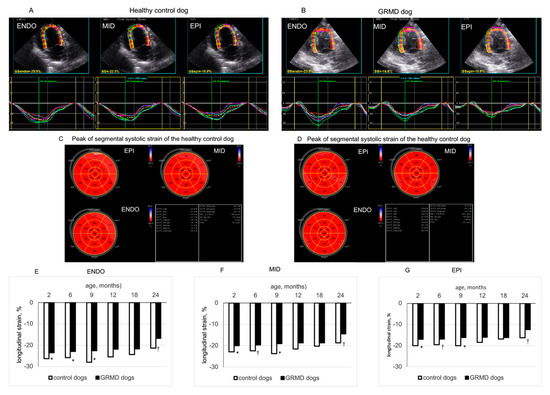

3.3. Changes in LS in the Three LV Wall Layers Analyzed by 2D-STE from the Three Apical Views in GRMD and Healthy Control Dogs at Different Ages

| 3C endocardial LS | Control | −28.8 ± 1.9 | −26.2 ± 1.7 | −25.8 ± 0.9 | −26.1 ± 0.8 | −23.5 ± 2.4 | −21.7 ± 1.1 | 0.0702 | 0.0010 |

| GRMD | −22.6 ± 0.6 † | −22.8 ± 0.8 * | −22.1 ± 1. 0 * | −21.9 ± 0.7 * | −22.1 ± 1.2 | −19.5 ± 1.7 | 0.3076 | ||

| 3C middle layer LS | Control | −24.0 ± 1.8 | −22.8 ± 1.5 | −22.3 ± 0.8 | −22.9 ± 1.0 | −20.3 ± 2.2 | −18.3 ± 0.6 | 0.1366 | 0.0007 |

| GRMD | −18.9 ± 0.5 † | −19.2 ± 0.6 * | −19.0 ± 0.7 * | −18.7 ± 0.8 * | −18.9 ± 0.9 | −16.7 ± 1.6 | 0.4422 | ||

| 3C epicardial LS | Control | −19.9 ± 1.7 | −19.9 ± 1.5 | −19.3 ± 0.7 | −20.1 ± 1.3 | −17.6 ± 2.1 | −15.5 ± 0.4 | 0.2452 | 0.0010 |

| GRMD | −15.9 ± 0.5 † | −16.3 ± 0.5 † | −16.5 ± 0.7 | −16.2 ± 0.6 * | −16.2 ± 0.7 | −14.4 ± 1.5 | 0.5367 | ||

| 4C endocardial LS | Control | −26.3 ± 1.3 | −25.7 ± 1.2 | −27.9 ± 2.1 | −25.4 ± 1.5 | −24.3 ± 0.6 | −21.4 ± 0.4 | 0.0881 | 0.0030 |

| GRMD | −23.5 ± 0.6 * | −22.9 ± 0.5 * | −22.5 ± 1.0 * | −21.7 ± 0.9 | −21.7 ± 1.3 | −16.8 ± 0.7 † | 0.0002 | ||

| 4C middle layer LS | Control | −22.8 ± 1.3 | −22.3 ± 0.9 | −23.7 ± 1.5 | −21.6 ± 1.2 | −20.3 ± 0.4 | −18.7 ± 0.5 | 0.0863 | 0.0034 |

| GRMD | −20.0 ± 0.5 * | −19.6 ± 0.4 † | −19.1 ± 0.9 * | −18.5 ± 0.8 | −18.7 ± 1.0 | −14.4 ± 0.7 † | 0.0002 | ||

| 4C epicardial LS | Control | −20.8 ± 1.4 | −19.6 ± 0.8 | −20.1 ± 1.0 | −18.4 ± 1.0 | −17.0 ± 0.5 | −16.3 ± 0.6 | 0.1023 | 0.0069 |

| GRMD | −17.0 ± 0.5 * | −16.9 ± 0.4 † | −16.2 ± 0.8 * | −16.0 ± 0.7 | −16.2 ± 0.8 | −12.5 ± 0.7 † | 0.0006 | ||

| 2C endocardial LS | Control | −26.0 ± 0.6 | −25.9 ± 0.9 | −25.2 ± 1.2 | −25.6 ± 1.0 | −22.6 ± 2.0 | −22.1 ± 1.2 | 0.0277 | 0.0054 |

| GRMD | −23.2 ± 0.5 † | −22.6 ± 0.5 † | −21.8 ± 0.7 * | −20.0 ± 0.8 † | −19.7 ± 1.3 | −19.4 ± 1.3 | 0.0006 | ||

| 2C middle layer LS | Control | −22.7 ± 0.6 | −22.2 ± 0.9 | −21.5 ± 1.2 | −21.7 ± 0.7 | −19.7 ± 1.4 | −19.6 ± 0.9 | 0.0746 | 0.0035 |

| GRMD | −19.5 ± 0.4 † | −19.6 ± 0.4 † | −19.0 ± 0.7 | −17.4 ± 0.7 † | −17.6 ± 1.2 | −16.7 ± 1.1 | 0.0088 | ||

| 2C epicardial LS | Control | −20.1 ± 0.5 | −19.1 ± 1.0 | −18.4 ± 1.5 | −18.3 ± 0.8 | −17.2 ± 1.1 | −17.5 ± 0.7 | 0.1672 | 0.0032 |

| GRMD | −16.4 ± 0.4 † | −17.2 ± 0.4 * | −16.8 ± 0.7 | −15.3 ± 0.6 * | −15.8 ± 1.0 | −14.4 ± 1.0 | 0.0398 | ||